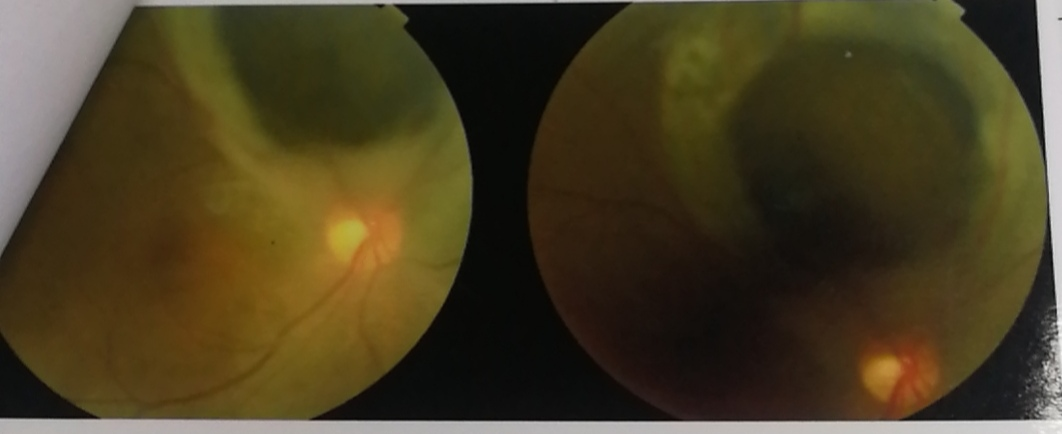

脉络膜黑色素瘤眼底表现

当时 , 林医生担心李依姆是视网膜脱落 , 进一步检查后 , 发现问题要更严重得多 。 老人患上了脉络膜黑色素瘤 , 眼睛四分之一都被肿瘤侵蚀了 。